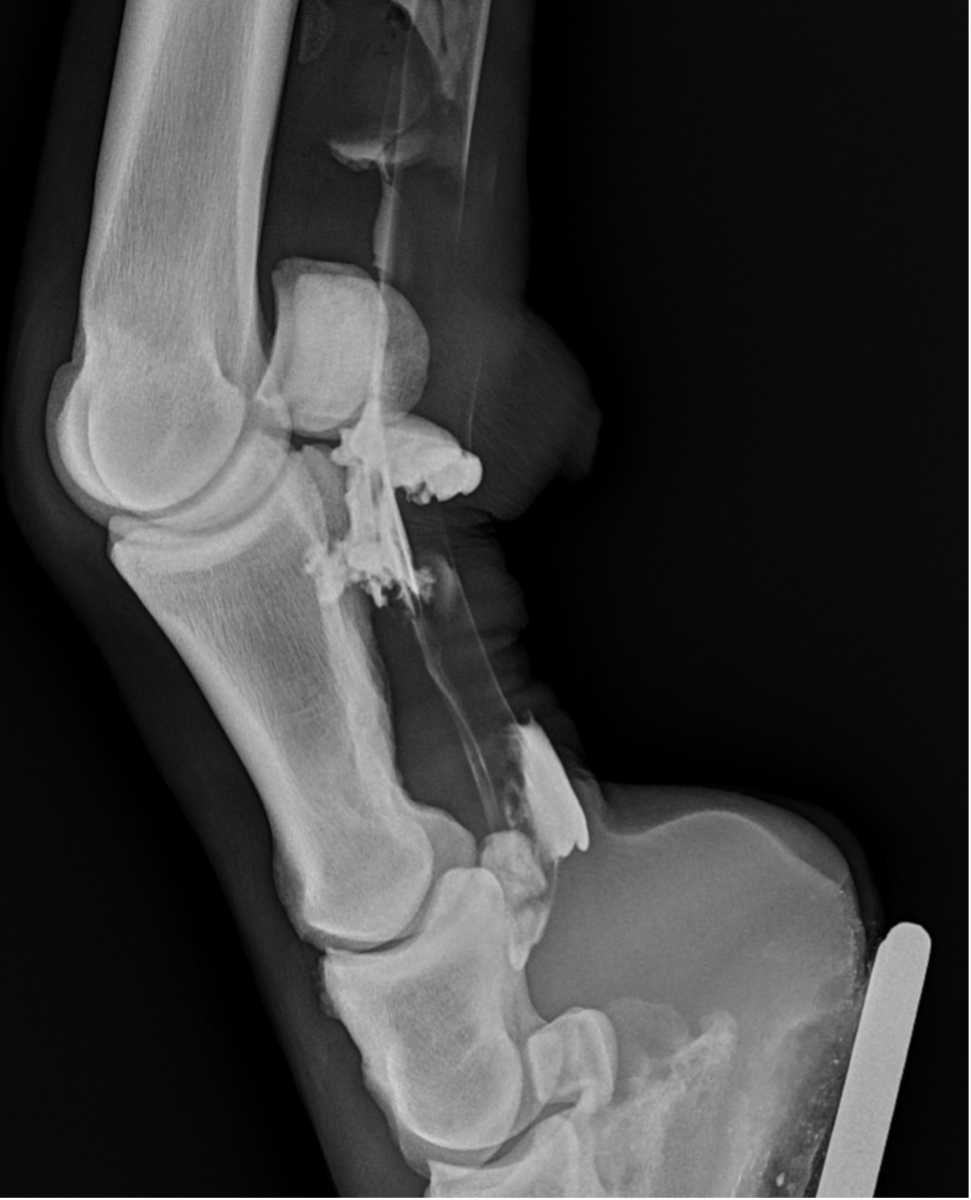

- The sheath is distended by anechoeic fluid. Arrow showing the swollen vincula and the arrowheads show swollen synovium surrounding the tendons.